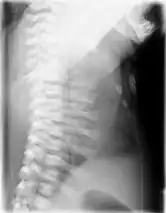

![]() | |

| CXR of a newborn with asphyxiating thoracic dysplasia. Note the short ribs. | |